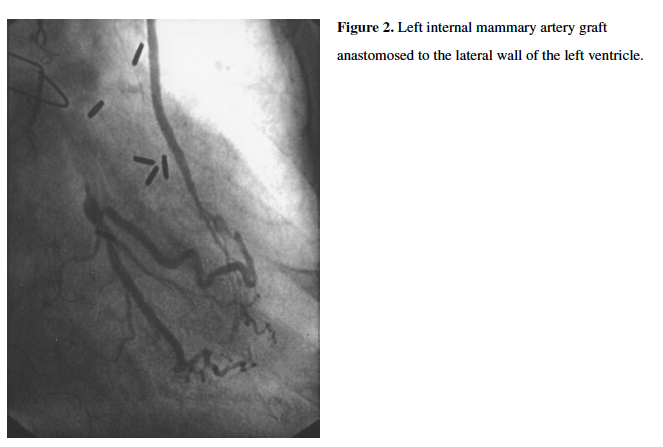

In January 2000, the patient underwent cardiac catheterization for progressively worsening exertional chest discomfort and dyspnea. Cardiac catheterization revealed triple-vessel disease with chronic occlusions of her ostial left anterior descending (LAD) artery, distal left circumflex (LCX) artery, and proximal right coronary artery (RCA). Both RIMA and LIMA grafts were patent. The RIMA had normal flow to the anterior LV wall, with vessel arborization and collateralization of the distal LAD and right posterior descending artery (PDA) as well as retrograde filling to the mid LAD (Figure 1). The LIMA was patent to the lateral LV wall with a similar appearing myocardial vascular network with direct collateral filling of the obtuse marginal (OM) and right posterolateral artery (PL) with retrograde flow to the distal left circumflex (Figure 2). On account of symptoms felt to be due to myocardial ischemia, she underwent redo sternotomy and CABG surgery, with reversed saphenous vein Y-grafting to a bifurcating obtuse marginal artery and a reversed saphenous vein graft (SVG) to the LAD. Approximately 1.5 hours after surgery, persistent and worsening hypotension prompted her cardiac surgeons to emergently perform redo sternotomy, during which she underwent repositioning of her SVG to the OM to remove a kink in her graft

She subsequently underwent further testing, including computed tomography (CTA) of her aortic root and bilateral iliofemoral arteries (aortic valve annulus, 369 mm2; 69 mm perimeter; 20.6 mm diameter; bilateral common iliac arteries with 5 mm mean luminal diameters), three-dimensional transesophageal echocardiography, and cardiac catheterization. Invasive coronary angiography revealed unchanged chronically occluded LAD, LCX, and RCA, and patent SVGs to the distal LAD and OM (Figures 3 and 4). Notably, the RIMA and LIMA grafts were somewhat atretic, but patent and with normal antegrade flow to the anterior and lateral LV myocardium, respectively (Figures 5 and 6), despite competitive filling from patent SVGs.